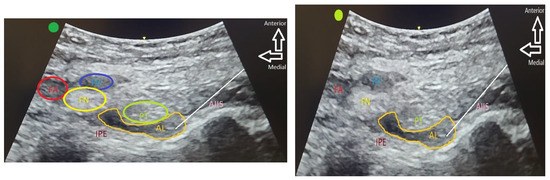

2.3. Intervention